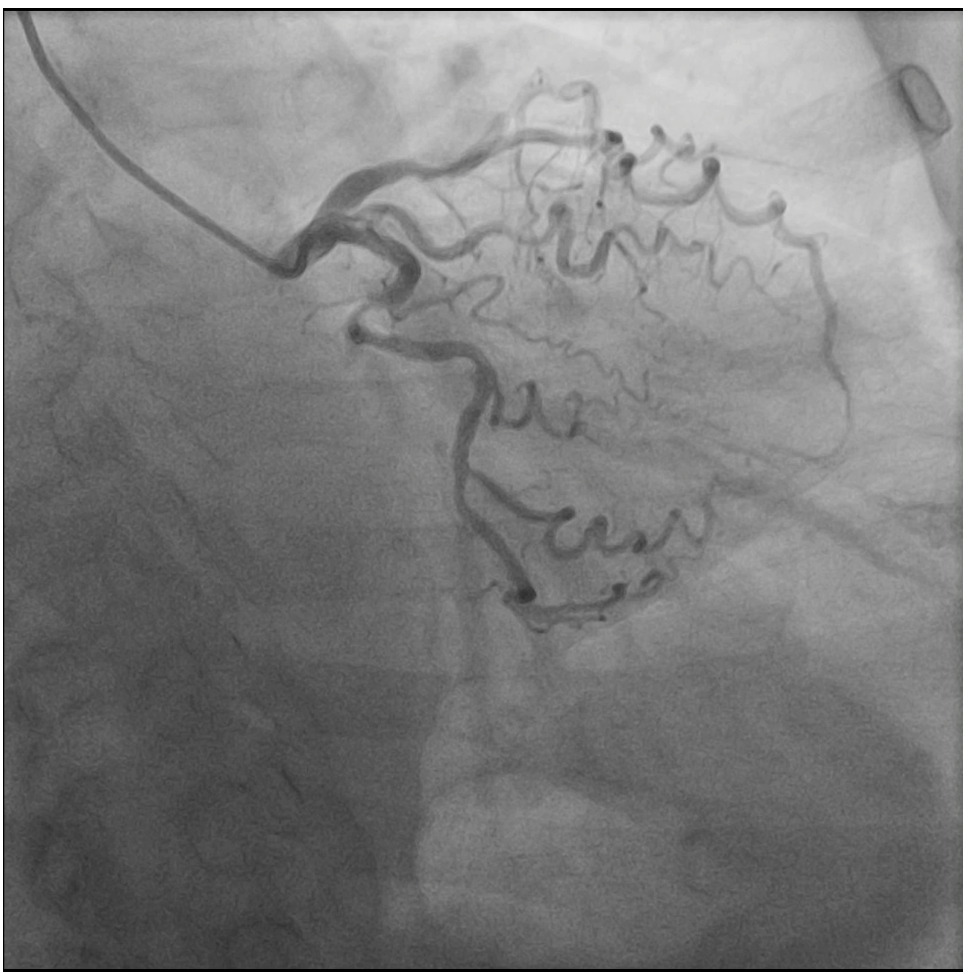

The diagnostic angiography demonstrated a severely tortuous coronary vessels, moderate lesion at LAD and LCX, total occlusion at proximal RCA with no traces of collaterals from the ipsilateral or contralateral circulations.

Several attempts to cross the lesion with workhorse wire and polymer jacketed wire with microcatheter support were failed because the wire went into small branch proximal to the occlusion. Guide catheter AL 0.75/7F was exchanged for JR 3.5/7F because of frequent pressure damping associated with deep engagement. Workhorse wire was left at the small branch while the second stiff wire was attempted to cross. The stiff wire (Gaia 2nd wire) and microcatheter was successfully cross and advanced to the distal. Microcatheter tip injection revealed contrast leakage to pericardial cavity. The stiff wire was exchanged for less traumatic workhorse wire and microcatheter was left to tampon the coronary perforation. Due to vague course of the vessel, rewiring to RCA was done with polymer jacketed wire in knuckle technique that eventually succeeded to cross the lesion and enter the true lumen. Pre-dilatation with semi-compliant balloon 2.5x15 mm at proximal-mid RCA was done to restore the flow. Angiography revealed tortuous and calcified RCA with some contrast leakage confined to pericardium. Subcutaneous fat embolization was attempted several times to seal the perforation. With minimal residual leakage, pre-dilatation with non-compliant balloon 3.0x18 mm was proceeded. Stent DES 3.0x38 mm was implanted at the proximal-mid RCA with the aid of 6F guide extension catheter. Angiography evaluation demonstrated good PCI result leaving only minimal residual contrast leakage confined to pericardium.